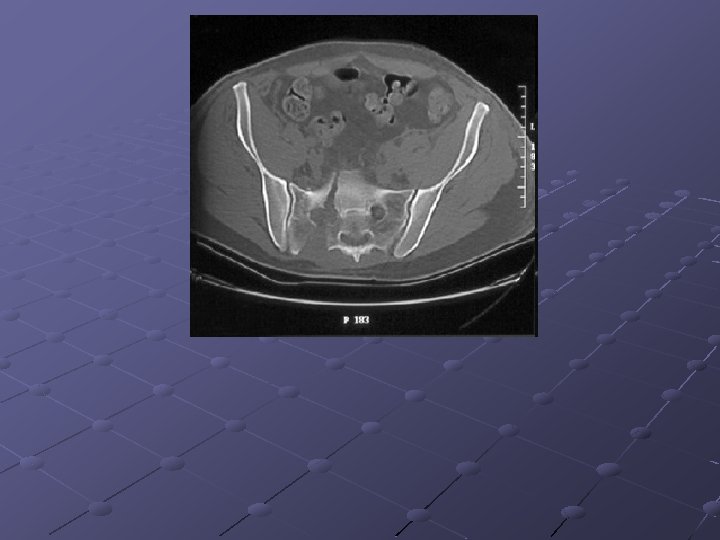

Imaging Studies